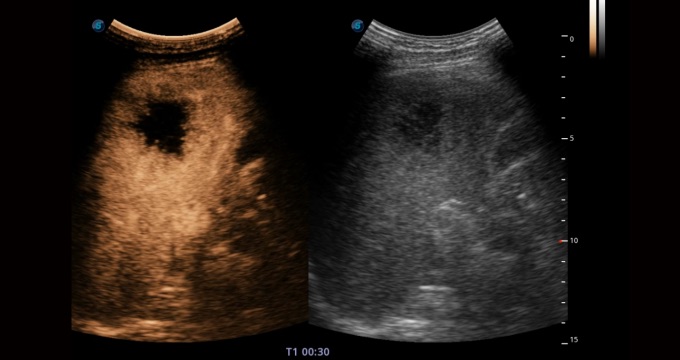

造影成像功能和定量分析工具包使醫(yī)生能夠準(zhǔn)確的評估血流灌注情況。獨(dú)特的動(dòng)態(tài)聲壓控技術(shù)有效控制造影劑的聲壓,保證造影劑持續(xù)時(shí)間,方便醫(yī)生觀察病變灌注的延遲相位。